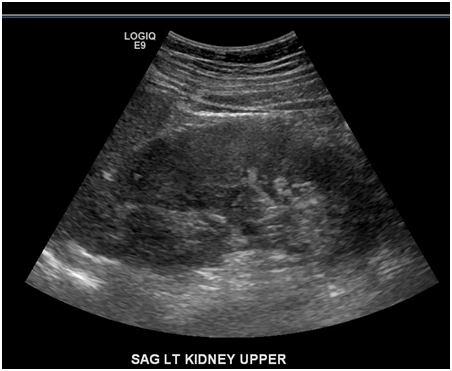

IV Contrast enhanced CT scan of the abdomen and pelvis showed consistent with acute pyelonephritis on the right side with an area of low-attenuation in the upper pole, measuring up to 2.4 cm, which may represent a developing abscess (Figure 3). Patient was started on intravenous Ceftriaxone 1gm every 24 hours and normal saline for IV hydration along with IV analgesics. In the first 24 hours of admission patient was noted to have high grade fevers up to 104.2°F. Urine cultures from a clean catch urine specimen grew Klebsiella pneuomoniae>100,000 CFU/ml which was sensitive to all tested antibiotics.

Figure 3 Computed tomographic image with intravenous contrast of abdomen and pelvis of case 2 showing right- Heterogeneous enhancement with perinephric fat stranding, with an area of low-attenuation in the upper pole, measuring up to 2.4 cm which may represent a developing abscess.